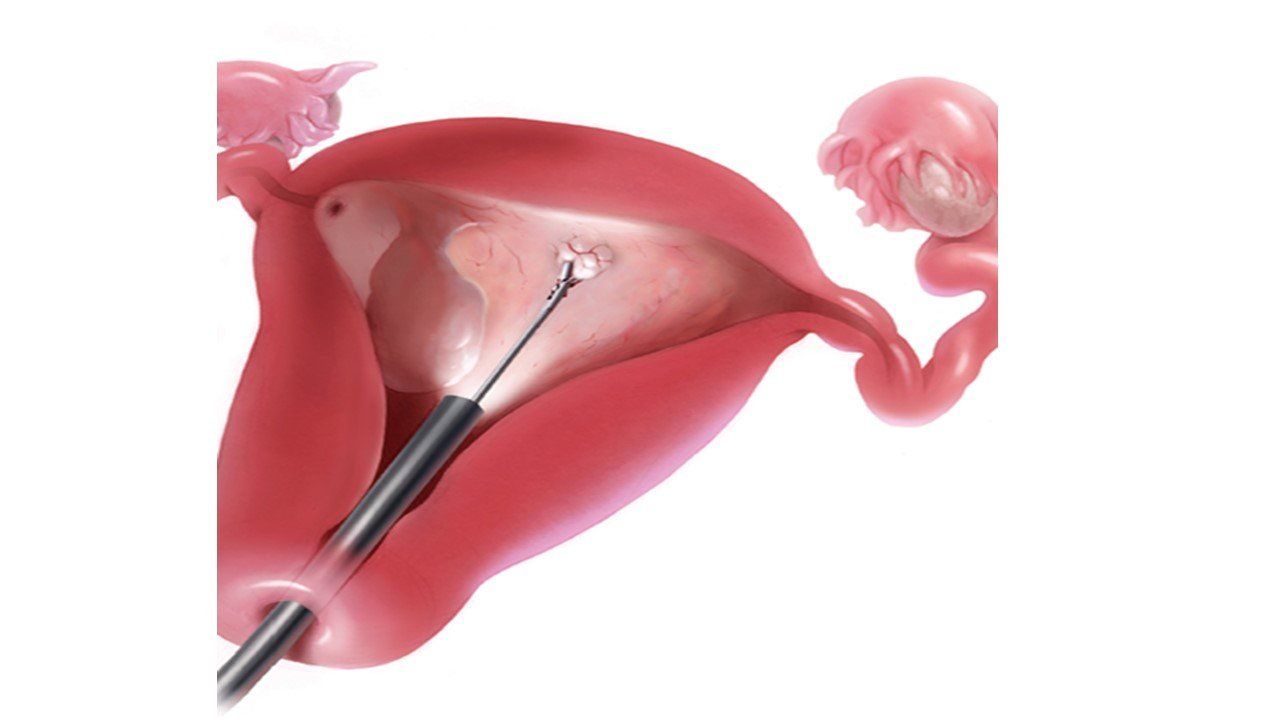

HISTEROSCOPIA: DIAGNÓSTICA Y QUIRÚRGICA.

HISTEROSCOPÍA DE CONSULTORIO: contamos con un sistema de origen alemán, tipo BETTOCCHI, de 2.9 mm de diámetro, que facilita la visualización directa del canal cervical y de la cavidad uterina, sin necesidad de dilatación del cuello uterino ofreciendo confort a la paciente. Con este procedimiento podemos diagnosticar y tratar gran parte de la patología uterina intra-cavitaria que son causas de dolor, sangrado e infertilidad; como:

- Pólipos y miomas.

- Biopsias endometriales.

- Adherencias.

- Cáncer de endometrio.

- DIU extraviados.

- Hemorragias anormales.

- Eliminación de septos uterinos.

- Extracción de cuerpos extraños.

- Dismenorrea.

RESECTOSCOPÍA BIPOLAR: contamos con resectoscopio híbrido con tecnología alemana, de 18 Fr (6mm de diámetro) que permite el procedimiento quirúrgico ambulatorio.